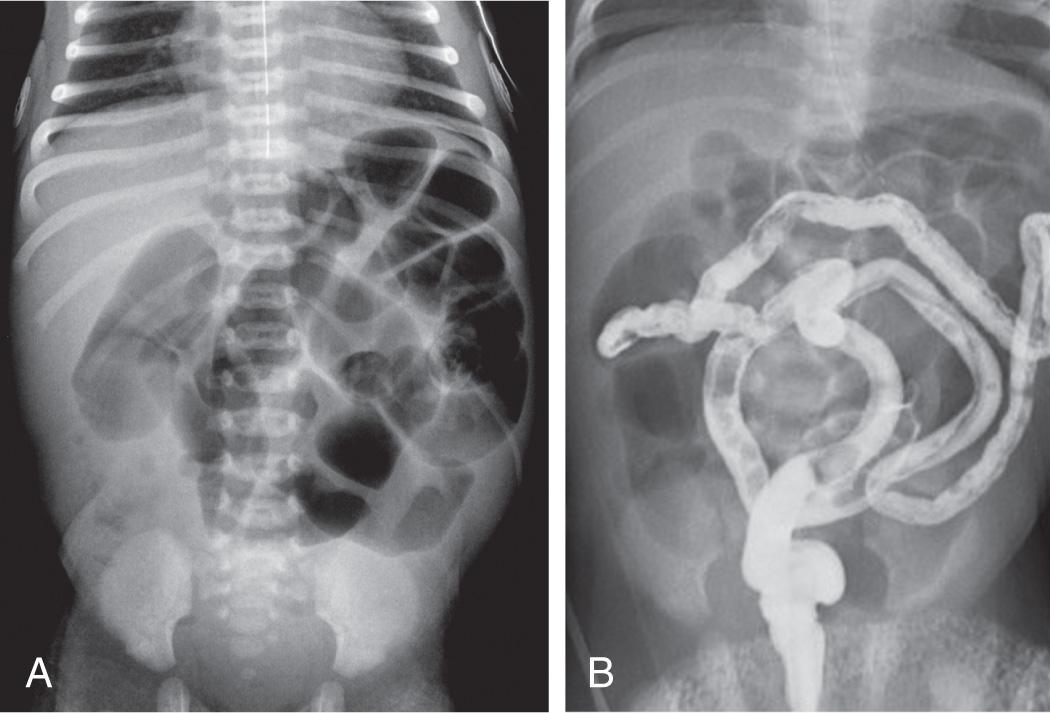

A very high index of suspicion in treating preterm at-risk infants is crucial. Plain abdominal radiographs are essential to make a diagnosis of NEC. The finding of pneumatosis intestinalis (air in the bowel wall) confirms the clinical suspicion of NEC and is diagnostic; 50–75% of patients have pneumatosis when treatment is started ( Fig. 123.5 ). Portal venous gas is a sign of severe disease, and pneumoperitoneum indicates a perforation ( Figs. 123.6 and 123.7 ). Ultrasound with Doppler flow assessment may be useful to evaluate for free fluid, abscess, and bowel wall thickness, peristalsis, and perfusion.

Fig. 123.7, Necrotizing enterocolitis (NEC).

The differential diagnosis of NEC includes specific infections (systemic or intestinal), GI obstruction, volvulus, and isolated intestinal perforation. Idiopathic focal intestinal perforation can occur spontaneously or after the early use of postnatal corticosteroids and indomethacin. Pneumoperitoneum develops in such patients, but they are usually less ill than those with NEC.

The patient's course should be monitored closely by means of frequent physical assessments; sequential anteroposterior and cross-table lateral or lateral decubitus abdominal radiographs to detect intestinal perforation; and serial determinations of hematologic, electrolyte, and acid-base status. Gown and glove isolation and grouping of infants at similar increased risks into cohorts separate from other infants should be instituted to contain an epidemic.

A surgeon should be consulted early in the course of treatment. The only absolute indication for surgery is evidence of perforation on abdominal radiograph (pneumoperitoneum) present in less than half of infants with perforation or necrosis at operative exploration. Progressive clinical deterioration despite maximum medical management, a single fixed bowel loop on serial radiographs, and abdominal wall erythema are relative indications for exploratory laparotomy. Ideally, surgery should be performed after intestinal necrosis develops but before perforation and peritonitis occur. The optimal surgical approach, however, remains controversial. The options for surgical treatment include primary peritoneal drainage (PPD) or exploratory laparotomy with resection of the necrotic intestine and usually stoma creation. Two randomized clinical trials in the mid-2000s comparing these approaches failed to demonstrate significant differences in survival, nutritional outcomes, or length of stay. A Cochrane analysis combining the results of both trials concluded that there were no significant benefits or harms of PPD over exploratory laparotomy. A 3rd randomized clinical trial (Necrotizing Enterocolitis Surgery Trial, NCT01029353) compares the 2 surgical approaches, with the primary outcome being death or neurodevelopmental outcomes at 18-22 mo adjusted age. A large, multicenter cohort study of 8,935 patients demonstrated that laparotomy was the initial therapy in two thirds of VLBW infants with surgical NEC, even in those <1,000 g. Mortality was about 30% in both the laparotomy group and the PPD-converted-to-laparotomy group (46% of PPD group eventually required laparotomy). PPD was found to be an independent risk factor for death (50% mortality), likely from its preferential use in the more seriously ill, unstable patients; however, 27% of patients undergoing PPD survived without further surgery. The surgical approach depends on surgeon preference and physiologic status of the patient.